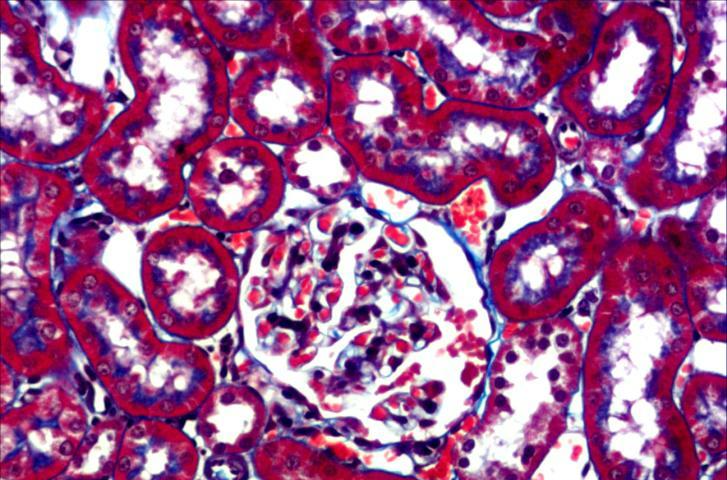

MT染色

Masson染色(MT染色)是結締組織染色中最經典的一種方法,又稱馬松染色,是顯示組織中纖維的主要方法之一,是膠原纖維染色權威而經典的技(jì)術(shù)方法。

該法染色原理(lǐ)與陰離子染料分子的大(dà)小(xiǎo)和(hé)組織的滲透有(yǒu)關,分子的大(dà)小(xiǎo)由分子量來(lái)體(tǐ)現,小(xiǎo)分子量易穿透結構緻密、滲透性低(dī)的組織;而大(dà)分子量則隻能進入結構疏松的、滲透性高(gāo)的組織。

然而,淡綠或苯胺藍(lán)的分子量都很(hěn)大(dà),因此Masson染色後肌纖維呈紅色,膠原纖維呈綠色或藍(lán)色,主要用于區(qū)分膠原纖維和(hé)肌纖維。